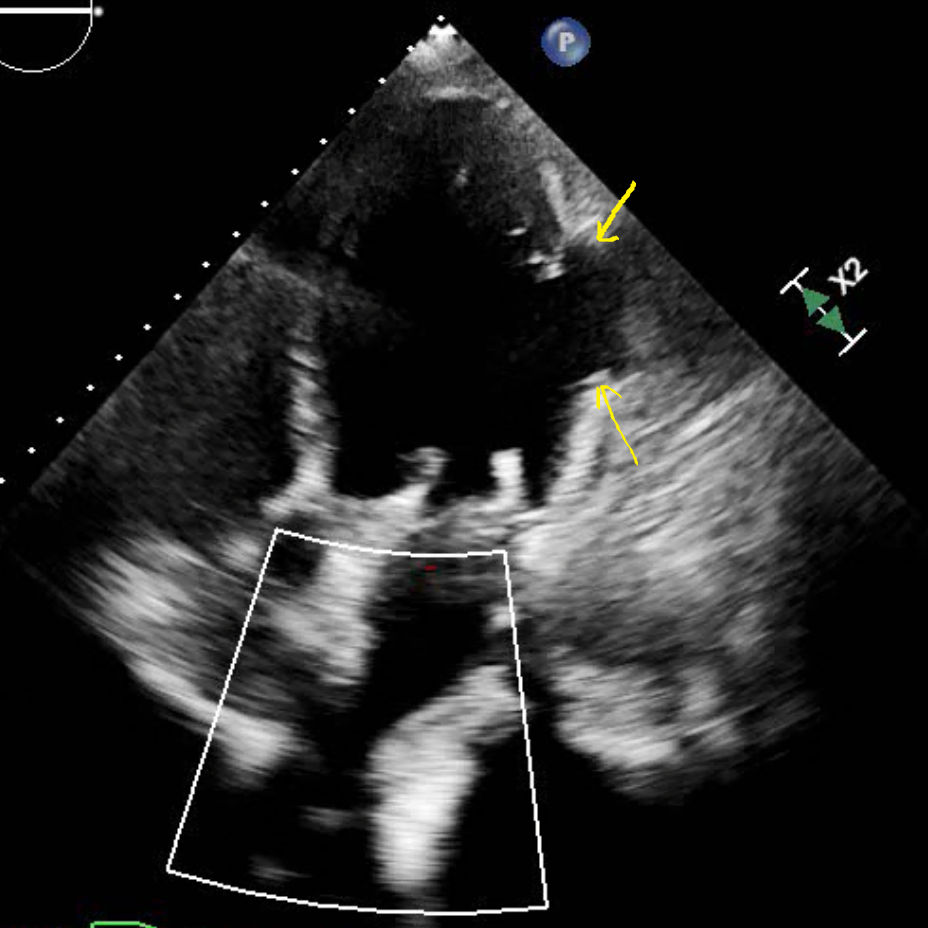

Echocardiogram (HLA view) shows obvious lateral wall aneurysm (yellow arrows)